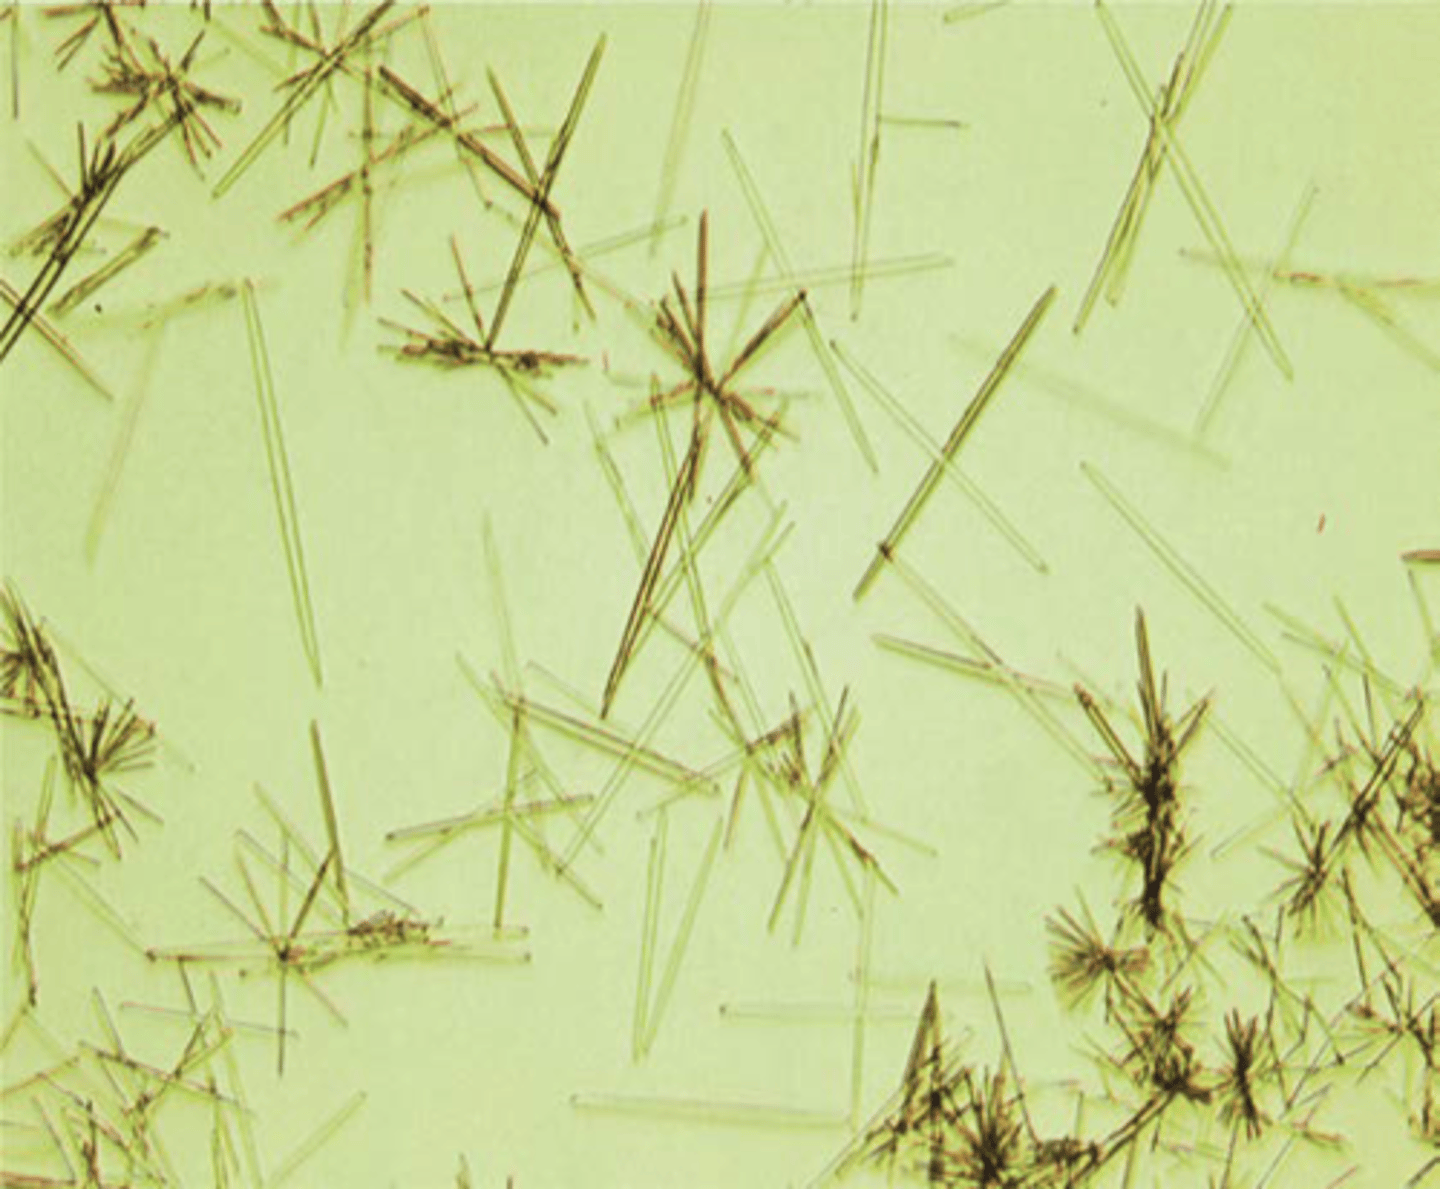

bundles of needle-like crystals (fan shape)

x ray dye crystals

urine

needle like